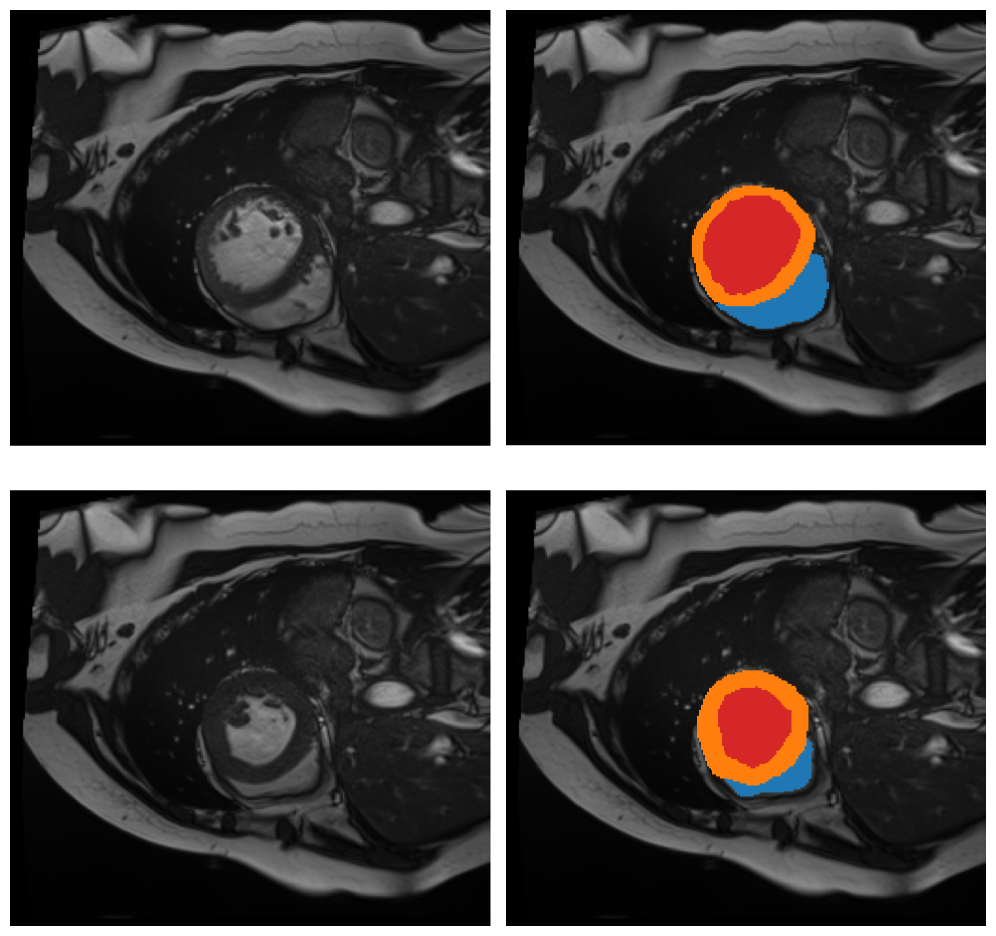

2.1.2 Myocardium

In clinical cardiology, it is essential to measure cardiac functions, such as volumes, mass of the ventricles, or thickness of the myocardium [40, 6]. These measurements are commonly obtained from segmented Cardiac Magnetic Resonance Imaging (CMR), which are multi-slice 2D MRIs, typically segmented in three classes: myocardium (Myo), left ventricular cavity (LV) and right ventricle (RV) [15, 10, 11], shown in Fig. 3.

We will use the Automated Cardiac Diagnosis Challenge (ACDC) dataset [23], part of MICCAI-ACDC 2017. It gathered 150 patients with diverse cardiac profiles (normal subjects, systolic heart failure, dilated or hypertrophic cardiomyopathy). The dataset contains, for each patient, two CMR scans: one at end-diastolic (ED) and one at end-systolic (ES) phase. The ground-truth segmentations, encompassing Myo, LV and RV, were drawn and double-checked by two experts.

CMR segmentation involves specific challenges: the images are inherently noisy, due to the motion of the heart; they present large variability from one patient to another; and the myocardium is surrounded by tissues of similar intensity, making its segmentation delicate. On the other hand, the ventricular cavities, through which blood flows, appear significantly luminous—an important feature for automatic detection.

In order to adapt our method described in Section 4 to cardiac segmentation, two specific issues must be addressed. First, the whole object—the union of the myocardium and the two ventricles—has heterogeneous intensity and hence cannot be selected as a whole via Module 1. Second, the myocardium forms a cylinder, which is topologically equivalent to a circle. Therefore, a representative cycle for the homology of a cylinder may not yield the entire cylindrical structure but only a subset of it. To address these issues, we first devise a two-dimensional version of our method, applied slice by slice. In this setting, each short-axis slice contains a roughly circular myocardium, so the topological complexity of the full 3D cylinder is avoided, and only the intensity heterogeneity problem needs to be handled.

In a slice , and as already visualized in Fig. 3, both ventricles appear hyper-intense and the myocardium hypo-intense. Moreover, the latter is surrounded by structures that are equally weak in intensity, making it impossible to estimate the union myocardium/ventricles by a simple superlevel set selection. To circumvent this issue, we will first identify the ventricles and then deduce the myocardium.